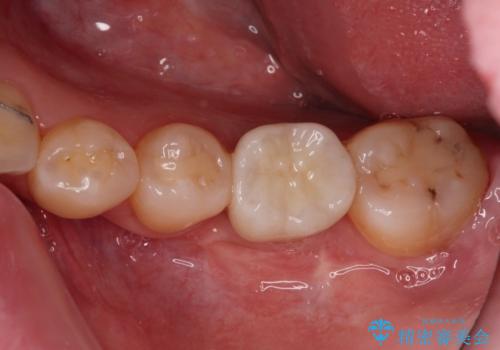

虫歯と抜いたままの奥歯とデコボコの前歯 総合歯科治療

- 放置した虫歯や抜いたままの奥歯、前歯のデコボコを気にして来院された患者様です。

口元の突出感は少なく、下顎の叢生は軽微なものであったので、叢生の強い上顎左右の小臼歯を1本ずつ抜歯し、ワイヤー装置にて矯正治療を行うこととしました。

矯正治療を行う前に、根管治療の必要な上顎前歯と下顎大臼歯の根管治療を行い、矯正治療の途中で下顎の欠損部にインプラント埋入することとし、矯正治療後に補綴治療を行うこととしました。

矯正治療中にインプラント埋入を行うなど、余計な時間や無駄のない治療を行うことができました。